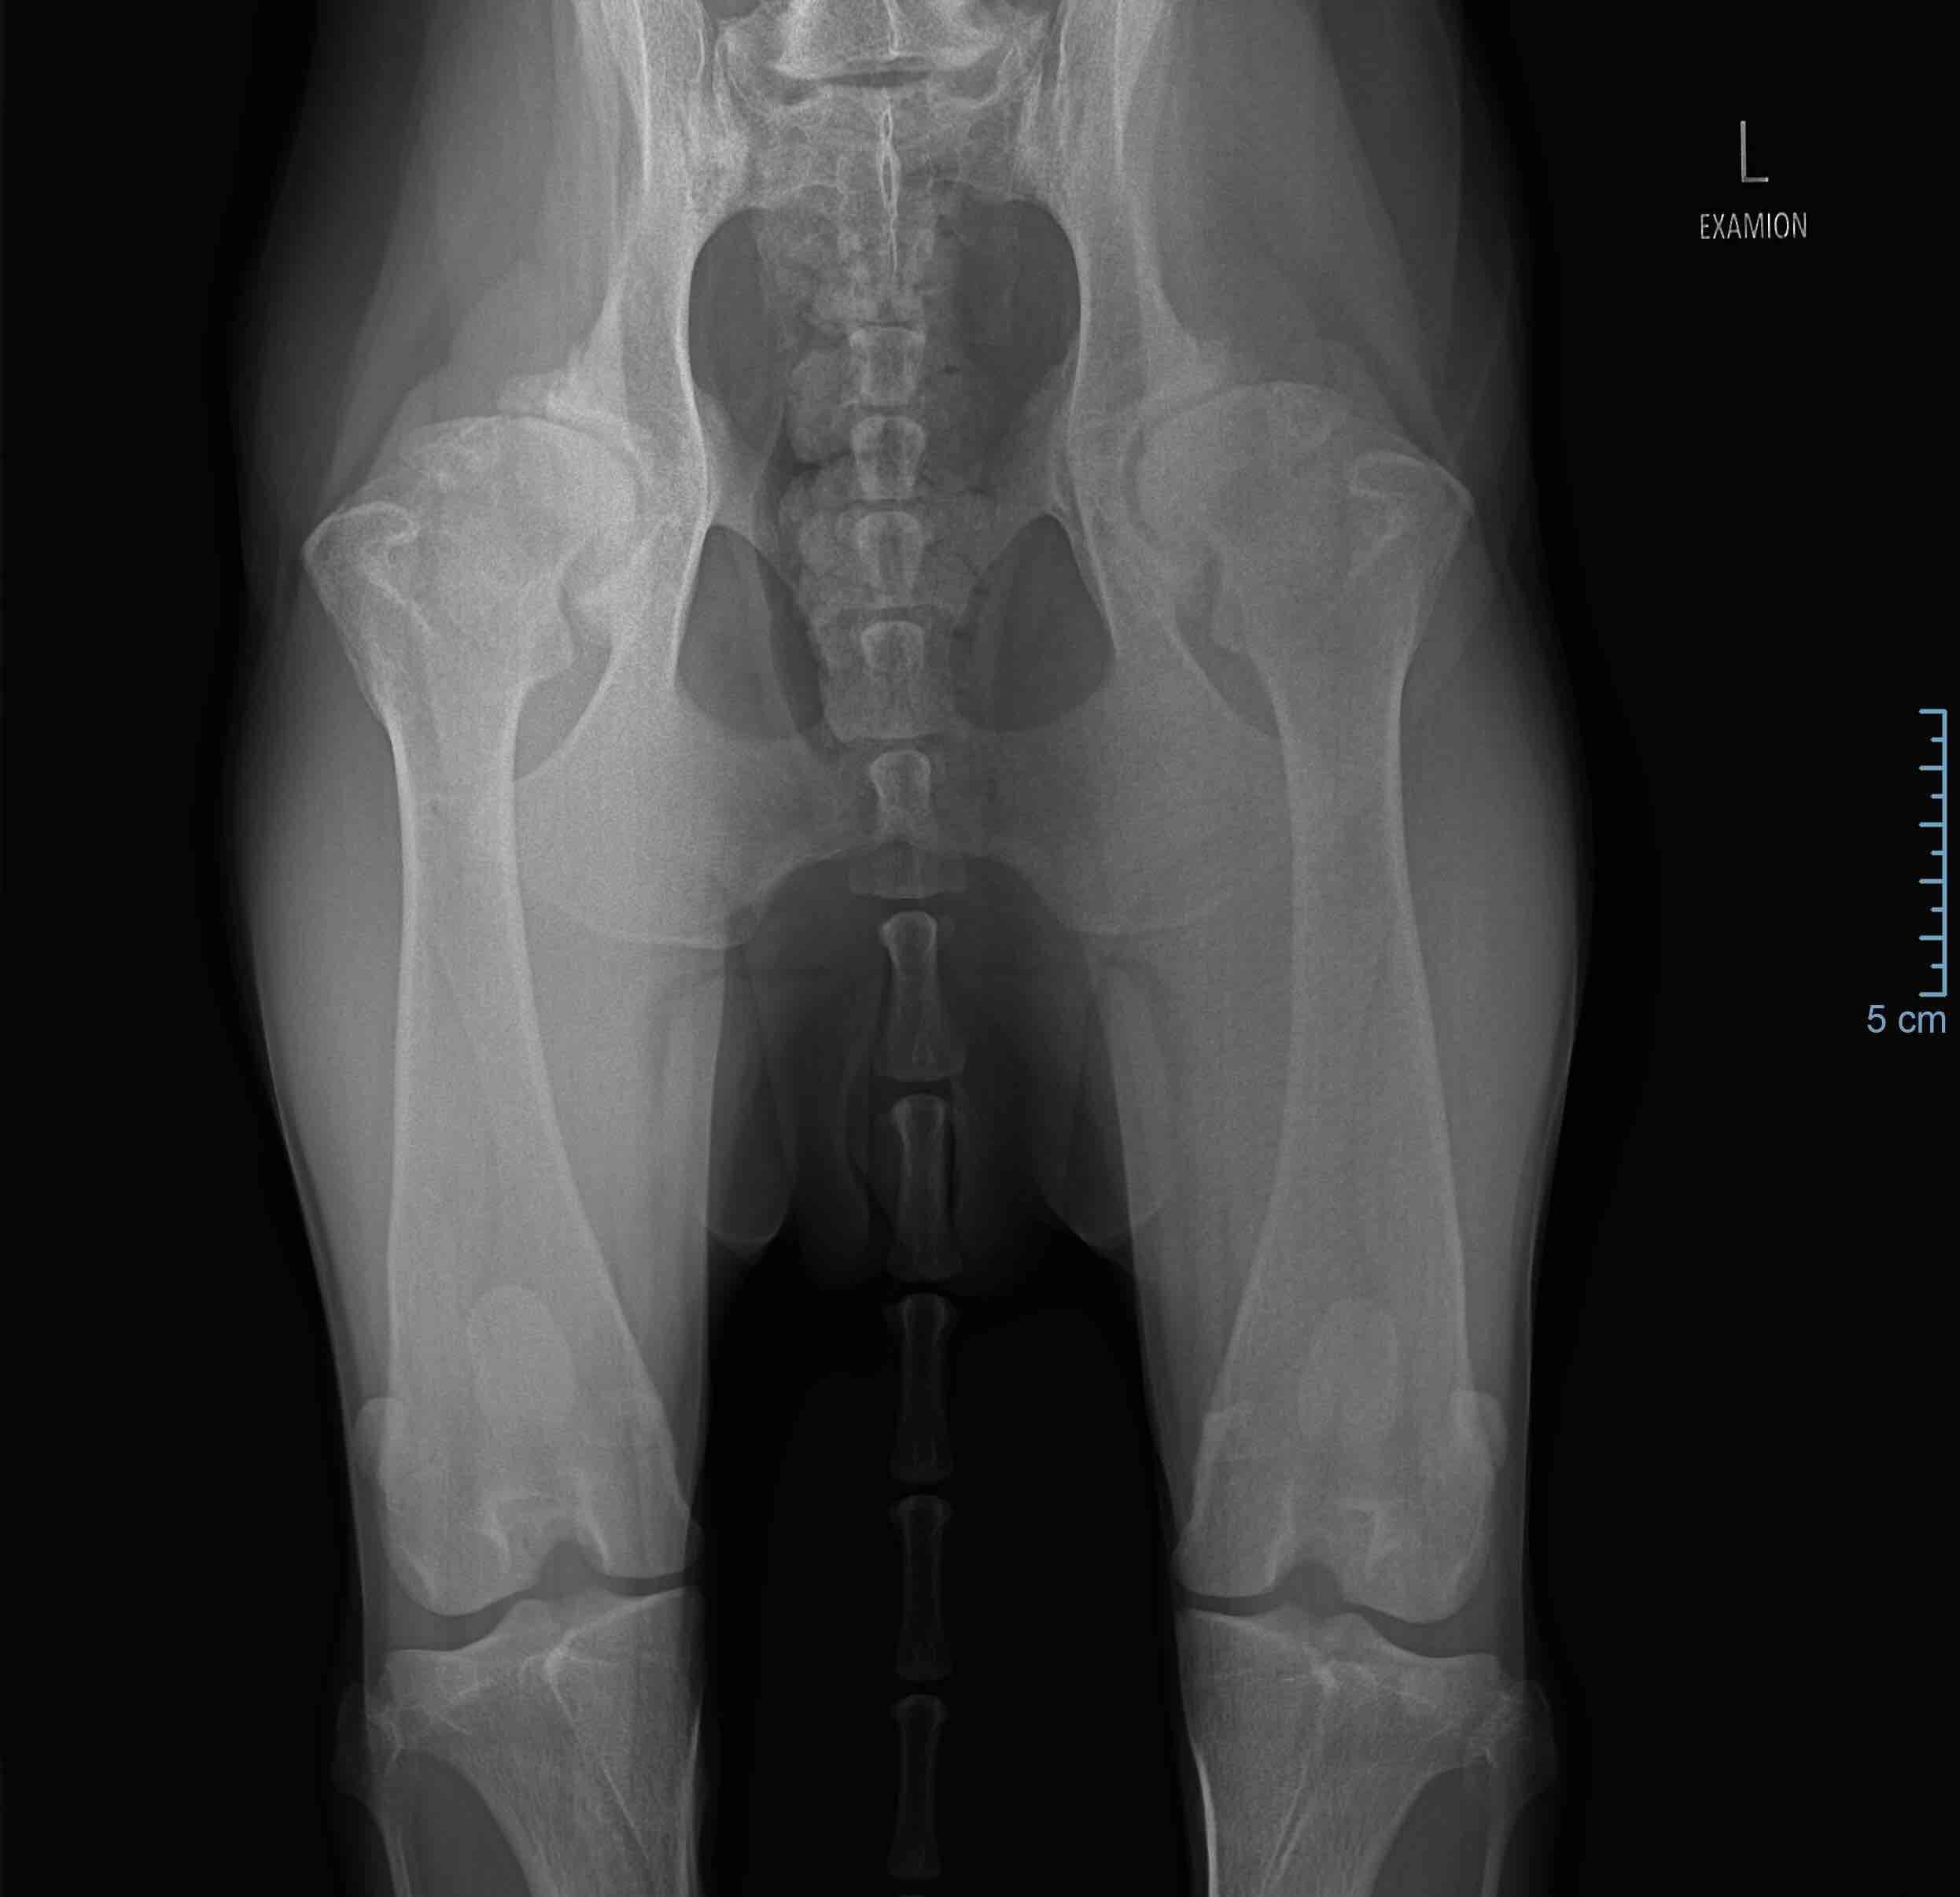

My Lab (32kg, age of 7) is diagnosed with Coxarthrosis. Current options are monthly injection of pain-killer, gold bead implantation and hip replacement. What will be the best option for the dog? Hip replacement sound risky and painful for the dog, but pain management isn’t curing the root cause of the problem.

Hello, thank you for using Petco Pet Education Center, formerly Petcoach. Sorry to hear that Nina has this issue. Hip replacement is always the best option if they are determined to be a good anesthetic candidate. The surgery is very commonly done and while all surgery is painful, in the long run it is the best option. If you ask human patients how they feel after hip replacement surgery, the vast majority will say they wish they had done it sooner as they feel so much better. That being said, typically dogs will still need some type of pain medication/anti-inflammatories after surgery, definitely short term but maybe even long term. There is no way to know this ahead of time. Hope this helps. Best wishes.